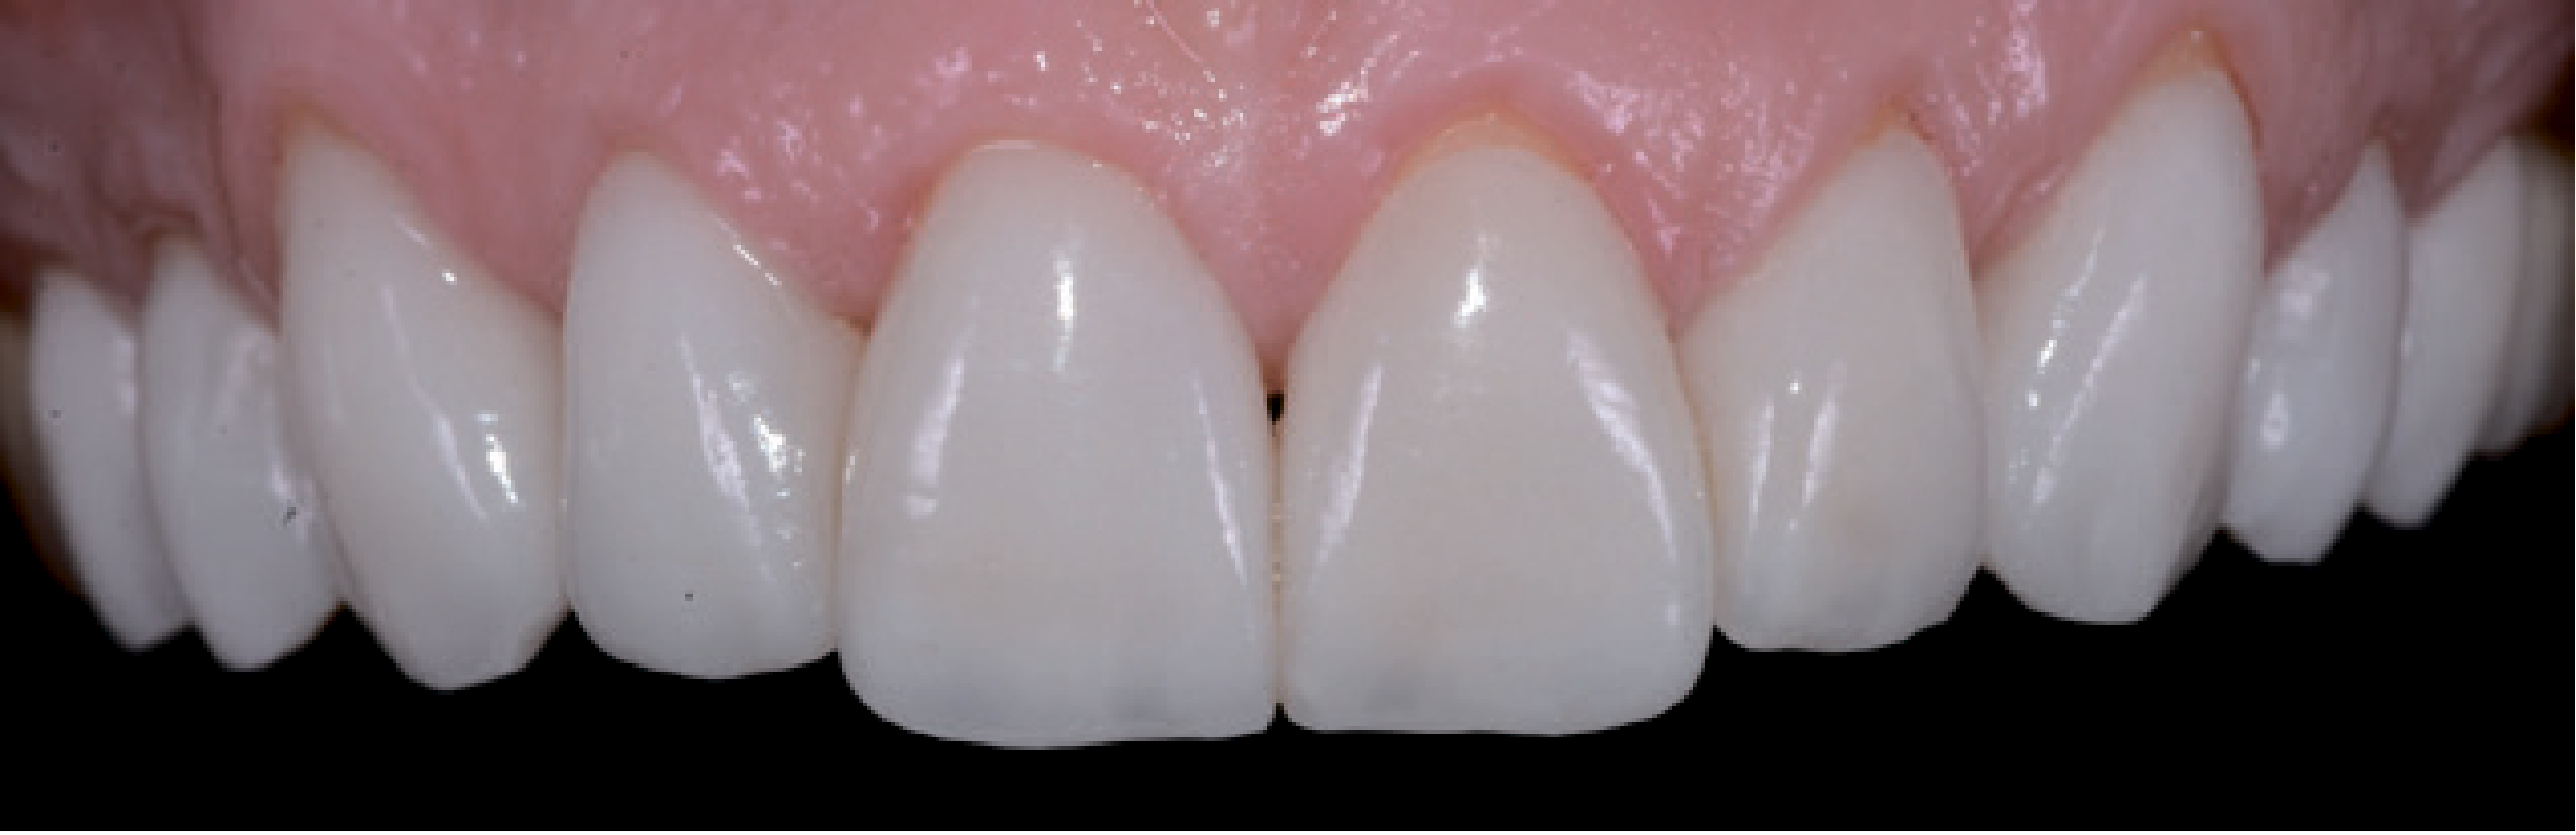

У стоматологічній лабораторії для зубів 15-25 були виготовлені пресовані вініри e-max, покриті полевошпатною порцеляною. Завдяки використанню техніки «spot etch» тимчасові реставрації вдалося легко видалити скалером. Відпрепаровану поверхню очистили матеріалом ConsepsisScrub (Ultradent). Для остаточного встановлення реставраційних конструкцій скористалися VitiqueCementationSystem (DMG). За допомогою пробних паст різних відтінків, аналогічних адгезивним цементам, за допомогою системи Vitique можна у всіх подробицях змоделювати остаточний результат. Оскільки порцелянові вініри тонкі та прозорі, цьому етапу приділили максимум уваги. Щоб приміряти реставраційні конструкції, використовували примірочні пасти, які містять гліцерин і є у комплекті VitiqueCementationKit (DMG). Вони дозволяють ідеально змоделювати остаточний результат (мал. 17).

Коли посадка й колір вінірів були задовільними для пацієнта та лікаря, адгезивну фіксацію можна було виконати та отримати прогнозований результат. Кукси знову очистили струменем води, після чого зафіксували вініри. Вініри протравили 5% розчином фтористоводневої кислоти та силанізували системою з двох флаконів VitiqueSilane (DMG) для посилення міцності з'єднання. Протягом 20 секунд відпрепаровані ділянки перебували під впливом 37% фосфорної кислоти, щоб забезпечити адгезивне з'єднання з ТЕСО (DMG). Адгезивний засіб з одного флакона нанесли тонким шаром на 5 секунд. Перш за все, верхні центральні різці обробили одночасно, щоб гарантувати симетрію. Сусідні зуби закрили тефлоновою стрічкою (мал. 18).

Навіть досить кваліфіковані стоматологи зовсім не завжди вирішуються використовувати вініри для естетичної реставрації. Вони бояться не отримати бажаний естетичний результат, адже пацієнти дуже вимогливо ставляться до такої процедури, оскільки вони змушені чимало за неї заплатити. Психологічна сторона, пов'язана з естетичною зоною, є непередбачуваним фактором ризику. Завдяки двоетапній техніці прямого й непрямого mock-up естетичний результат можна обговорити з пацієнтом, а потім і реалізувати його за участю пацієнта. Коли модель mock-up виглядає достатньо переконливо для стоматолога й пацієнта, вона використовується як якісний орієнтир для отримання задовільного естетичного результату. Далі препарування виконується виключно в межах емалі – для надійної фіксації реставраційної конструкції адгезивним цементом на тривалий термін. З цієї причини згодом, щоб створити оптимальне з’єднання, поглиблення не препарували. У цьому випадку ці ділянки непомітні крізь лінію посмішки, і пацієнт не захотів, щоб контури виправляли мікрохірургічним шляхом. В інших випадках оптимізувати естетичний вигляд м'яких тканин можна за допомогою вільного слизового трансплантата. Новий сагітальний різцевий шлях був створений за допомогою вінірів, щоб не допустити впливу неконтрольованих зусиль. Вночі ж щелепно-ротовий апарат і реставраційні конструкції були захищені за допомогою верхньощелепної ортопедичної капи. Активне спілкування і взаємодія стоматолога з пацієнтом спочатку передбачає виконання додаткової роботи, проте допомагає швидко отримати прогнозований результат і виключити непередбачені витрати коштів і часу, а також непотрібний стрес і розчарування (мал. 21 і 22).